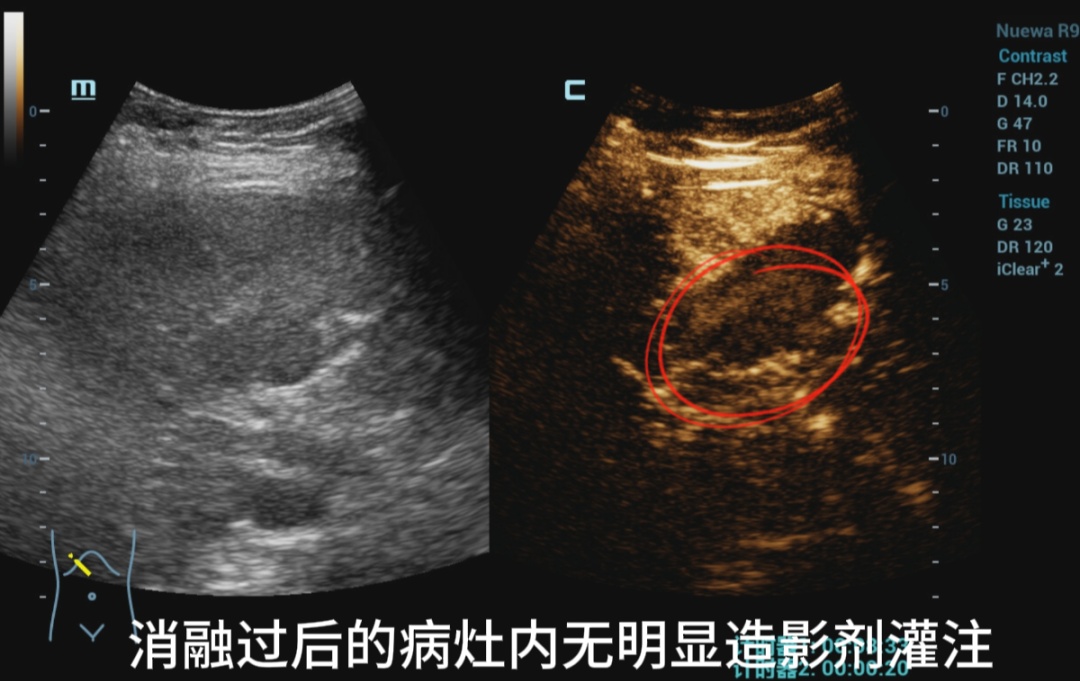

消融过后即刻打造影剂

评估消融效果

IVb段病灶

两病灶内均无明显造影剂灌注,消融效果满意。

患者出院前超声造影复查

复查结果提示未见肝内有强化病灶,肿瘤完全失去了活性。经外周静脉注射造影剂Sonazoid后,病灶区域始终未灌注区,显示消融效果满意。